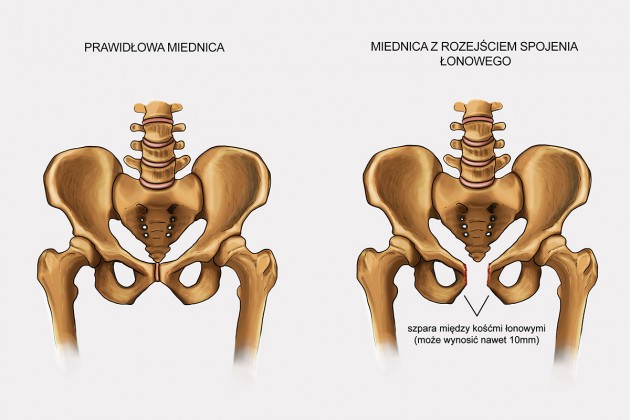

Rozejście spojenia łonowego jest zaś skutkiem nadmiernego rozluźnienia więzadeł i zwiększenia ruchliwości kości miednicy pod wpływem hormonów ciążowych (estrogenów). Hormony te wpływają zarówno na chrząstkozrost łonowy jak i stawy krzyżowo-biodrowe. Pojawia się ból w trakcie chodzenia („kaczy chód”), a niekiedy słyszy się nawet w trakcie chodzenia charakterystyczne trzaski. Niemożliwe staje się stanięcie na jednej nodze. Do rozejścia się spojenia łonowego (jak również jego pęknięcia a nawet rozerwania) może dojść w trakcie trudnego porodu, gdy istnieje niewspółmierność porodowa lub konieczne było użycie kleszczy.

– rozejście spojenia łonowego